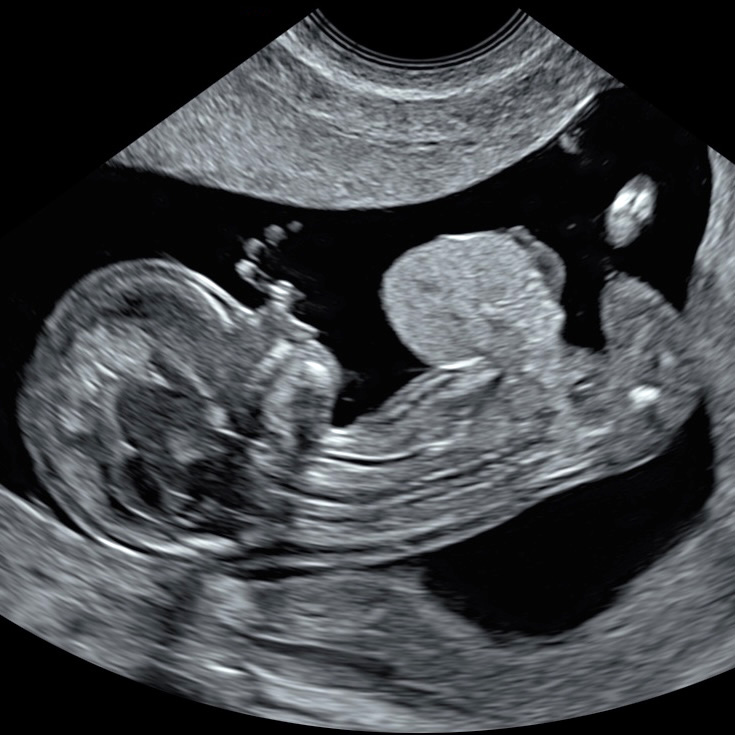

Combining the earliest structural screening for most severe anomalies with precise NT measurement in a single scan

At this early stage the baby is very small, so the scan is usually done through the vagina (transvaginal) to get the sharpest images. The transvaginal probe sits closer and uses higher-frequency sound, giving better resolution for tiny structures including the NT.

We can scan through the tummy (transabdominal) if the view is good, but detail is often lower because the beam travels further and is partly absorbed by the abdominal wall; we’ll use whichever gives the best view—both are safe.

We scan first to confirm NIPT is appropriate. Several early major anomalies like acrania, amniotic band syndrome, body-stalk anomaly, cloacal exstrophy, limb–body–wall complex, pentalogy of Cantrell, and sirenomelia, are usually non-genetic with a very poor prognosis.